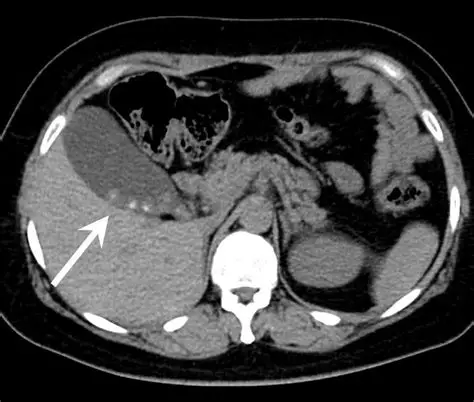

第3位:腎嚢胞(単純性)

📌 CTでよく書かれる表現

CT結果には、こんな記載がよく見られます。

- 「腎嚢胞を認める」

- 「腎に液体貯留を伴う嚢胞性病変」

「腎」「嚢胞」「病変」

この3ワードが並ぶと、一気に不安が跳ね上がるのも無理はありません。

🔍 単純性腎嚢胞とは?

単純性腎嚢胞は、

- 中身は「水」

- 年齢とともに増える

- がんとは全く別物

という特徴を持つ、いわば“加齢変化”のひとつです。

CTでは、

- きれいな丸い形

- 中が均一な液体

- 壁が薄い

といった所見がそろえば、

心配いらないタイプと判断されます。